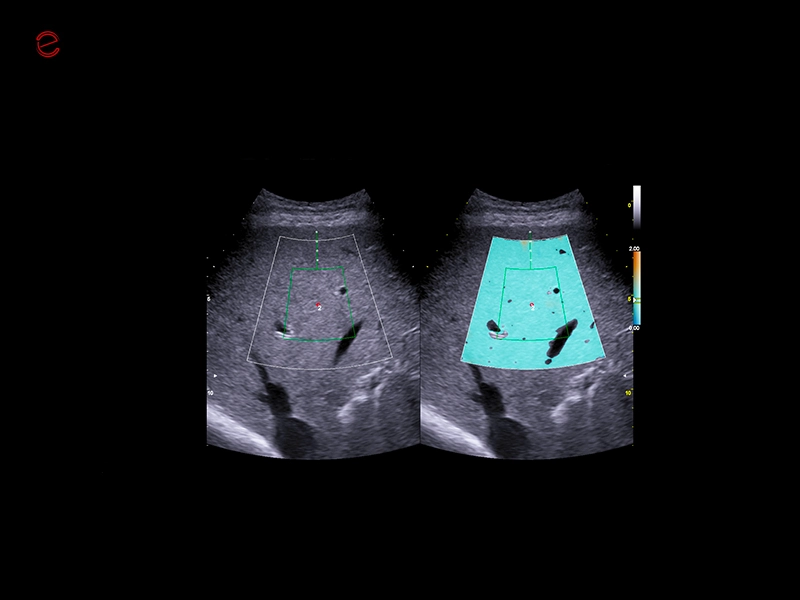

MyLab™E80 - QAI - Liver

MyLab™E80 - QAI - Liver